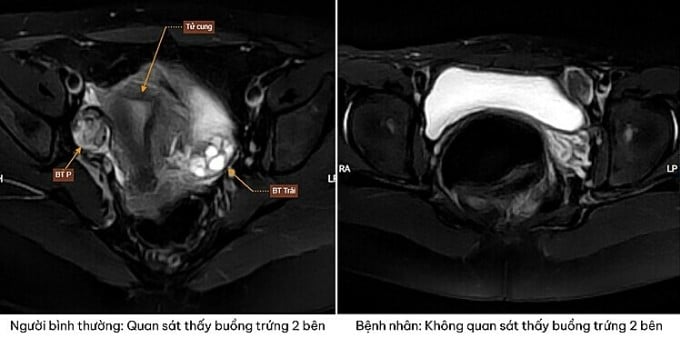

Kết quả siêu âm và chụp MRI cho thấy em không có tử cung và buồng trứng. Thay vào đó, bác sĩ phát hiện tổ chức nghi ngờ là tinh hoàn nằm trong ổ bụng. Xét nghiệm nhiễm sắc thể xác định bệnh nhân mang bộ 46, XY thuần. Điều này xác định người bệnh là nam về mặt di truyền, dù hình thái bên ngoài là nữ.